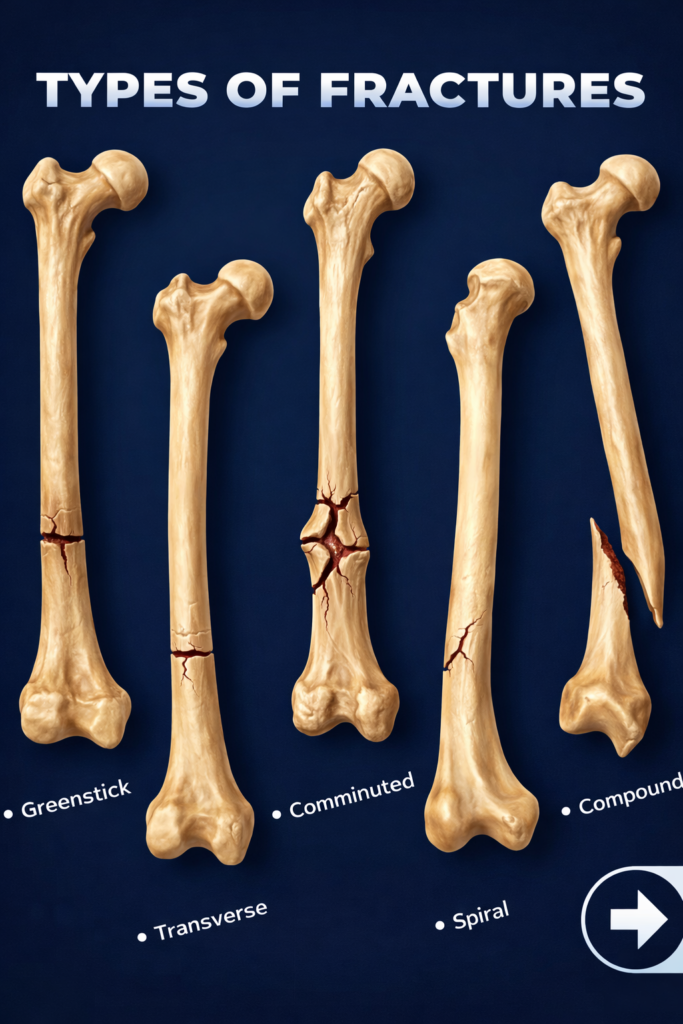

Types of Fracture Fixation Surgeries

Different fractures require different fixation methods. The choice depends on fracture location, severity, and stability.